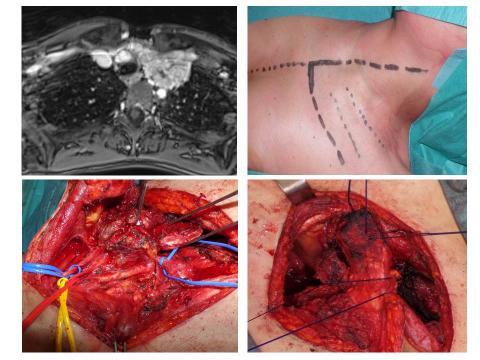

Chest wall resection and reconstruction